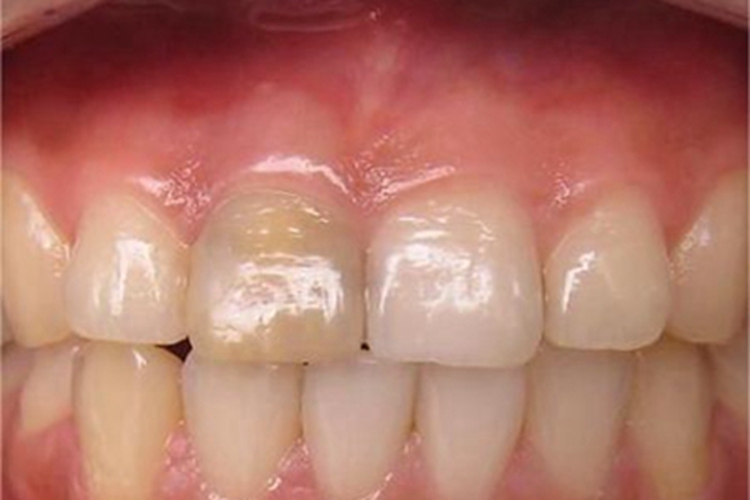

死髓牙患者一般没有自觉症状,仅以牙冠变色为主诉前来就诊。临床检查可以发现患牙牙冠存在深龋洞或是牙冠有重度的磨耗,牙冠变色,呈暗黄色或灰色,失去光泽;有穿髓孔的患牙,探查穿髓孔无反应。